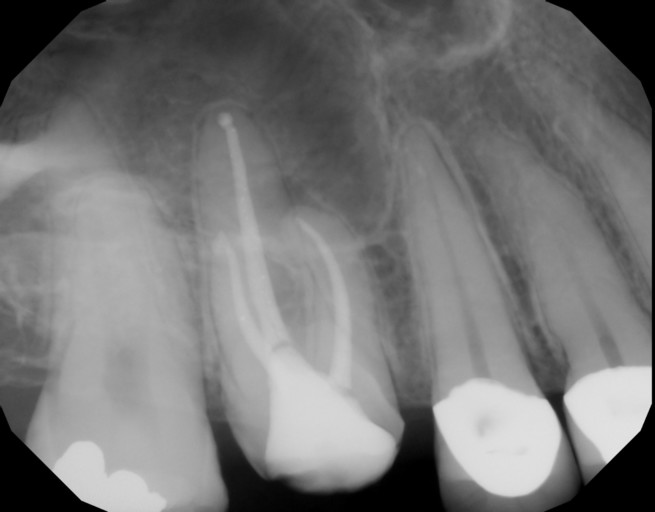

Hi,I reinjured one of my front teeth that was previously injured after a fall and was pushed back in my mouth 1 yr ago. I had it positioned back into place, got a root canal done and had splinter over it. But 2 weeks ago I reinjured the tooth and it got pushed back in my mouth again. It got positioned back in place but this time it hung lower than other teeth and is loose. Dentist said I have root reabsorption and should get it pulled. Is my roots broken? Can my tooth be tightened back up again and pushed upwards into gums? Or must I get it extracted? Will my tooth eventually fall out anyways if I decide to keep it? I really want it saved.